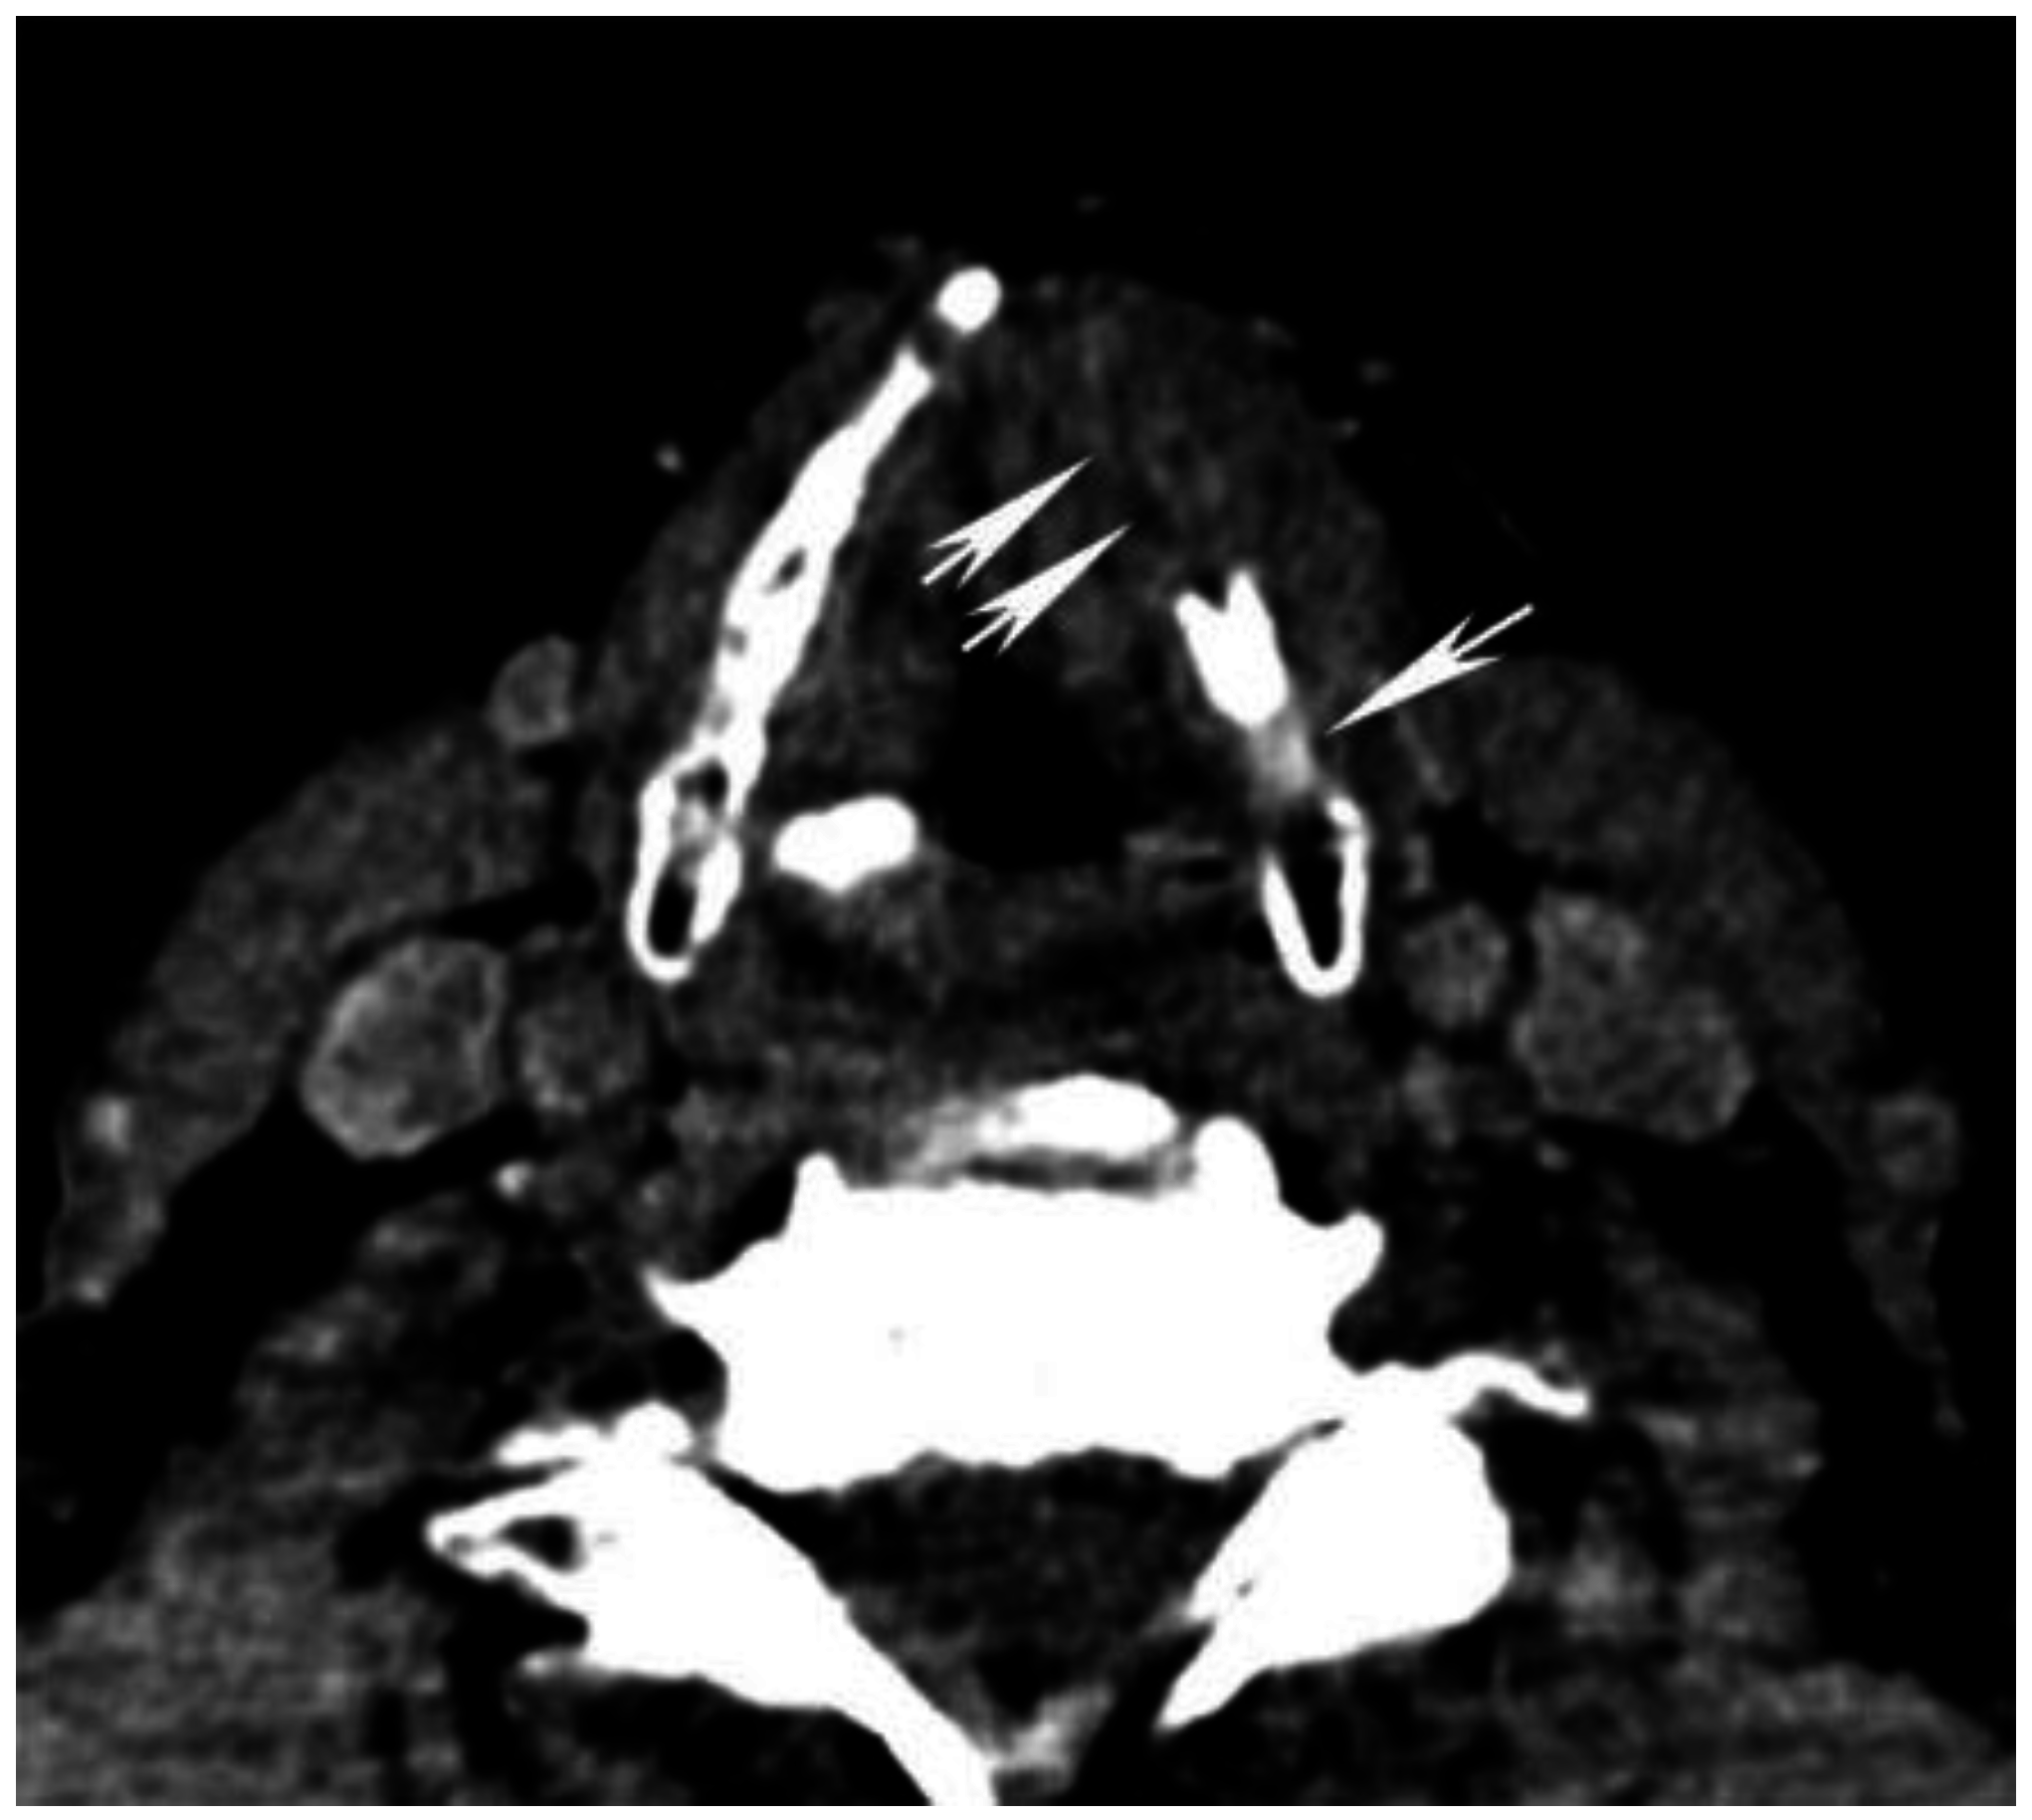

In clinical practice, imaging at higher peak voltage reduces the magnitude of artifacts, and may potentially represent an approach to improving the quality of CT imaging in patients with dental hardware. Using DECT to reconstruct VMIs that simulate imaging at higher energy levels may therefore reduce metallic artifact [53] (Figure 6 and Figure 7). This effect has been investigated in a number of in vivo and ex vivo studies using orthopedic hardware, and high energy VMIs have been shown to reduce metallic artifact significantly, both quantitatively and qualitatively, improving assessment of the implant, the surrounding bone, and soft tissue interface [51,52,53,56,57,58,61].

Figure 6. Use of high energy DECT virtual monochromatic images (VMIs) for dental artifact reduction. (A) 65 keV and (B) 140 keV VMIs are shown from the same level in the neck. Note significant reduction of artifact such as in the region of retromolar trigone (black arrow) or oral tongue (white arrow) on the higher energy, 140 keV VMI compared to the 65 keV VMI.

Figure 7. Use of high energy DECT virtual monochromatic images (VMIs) for dental artifact reduction in a patient with a gingival-buccal tumor. (A) 65 keV (equivalent to single energy CT) and (B) 95 keV VMIs are shown from the same level in the neck. Note reduction of artifact and improved visualization of the enhancing tumor on the 95 keV VMI compared to the 65 keV VMI.